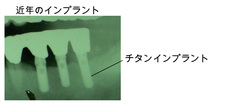

インプラントとは、歯を失った歯に代えて人工の歯根を、顎の骨に穴を開けて埋め込んで、その上に人工の歯を作って自分の歯の様な感覚で、噛めて、健康で快適な生活を取り戻すものです。

今回インプラントの使いまわしというあってはならない事件がありましたが、絶対にあってはならないことです。